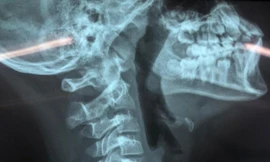

TPO - Ngày 7/5, tin từ Bệnh viện Đại học Y Hà Nội cho biết, sáng cùng ngày khi các bác sĩ của khoa Cấp cứu đang cấp cứu cho một bệnh nhân thì một nhóm côn đồ xông vào viện chém bệnh nhân đứt khí quản.